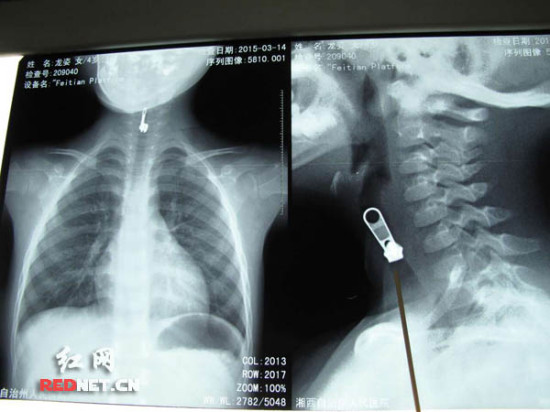

(X光片下,卡在女孩喉咙的拉链)

据龙先生回忆,女儿大约从十天前开始出现咳嗽、喉咙嘶哑、喉咙里呼呼作响等症状,还有些发烧。“在我们那边的医院看了,说是感冒,咽喉发炎了,开了药打了几天针总不见好”。3月14日,焦急的龙先生带着女儿赶到了湖南省儿童医院,接诊医生发现孩子可能是气管异物,马上给孩子进行了X光片检查。“片子一出来,吓了我一跳,孩子的脖子那里卡了一个拉链头,看得特别清楚,可它是怎么进去的呢”,龙先生说。这时,一旁的孜孜指着片子自己说:“这是我吃的”,才消除了龙先生的疑虑,“孩子不舒服至少十天了,想起来我就后怕”。

3月14日晚,经过连夜急诊手术,医生成功从孜孜气管内取出一枚长2.2厘米、宽6毫米、厚4毫米的金属拉链头。“拉链头正好卡在孩子的声门部位,由于它是不规则的物体,所以没有完全堵塞气道,但是反复的异物刺激会引起水肿,一旦水肿将气管完全堵塞,那就危险了”,手术医师、湖南省儿童医院耳鼻咽喉-头颈外科副教授黄敏介绍。